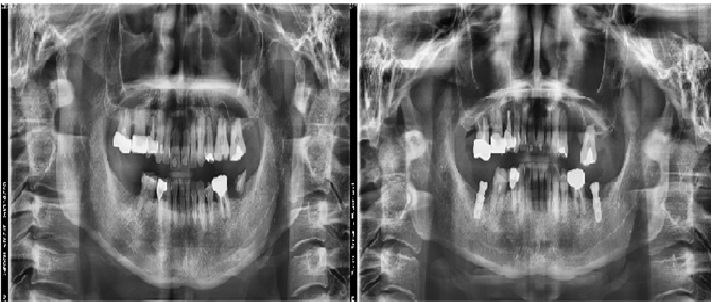

치료전후사진